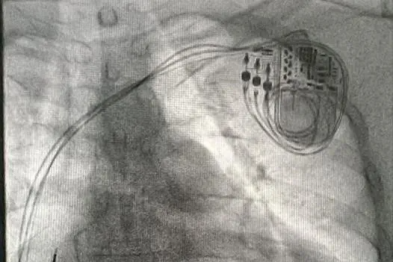

突破传统!胸骨下植入「心律哨兵」——湖北省第三人民医院完成全国首批 EV-ICD 植入术